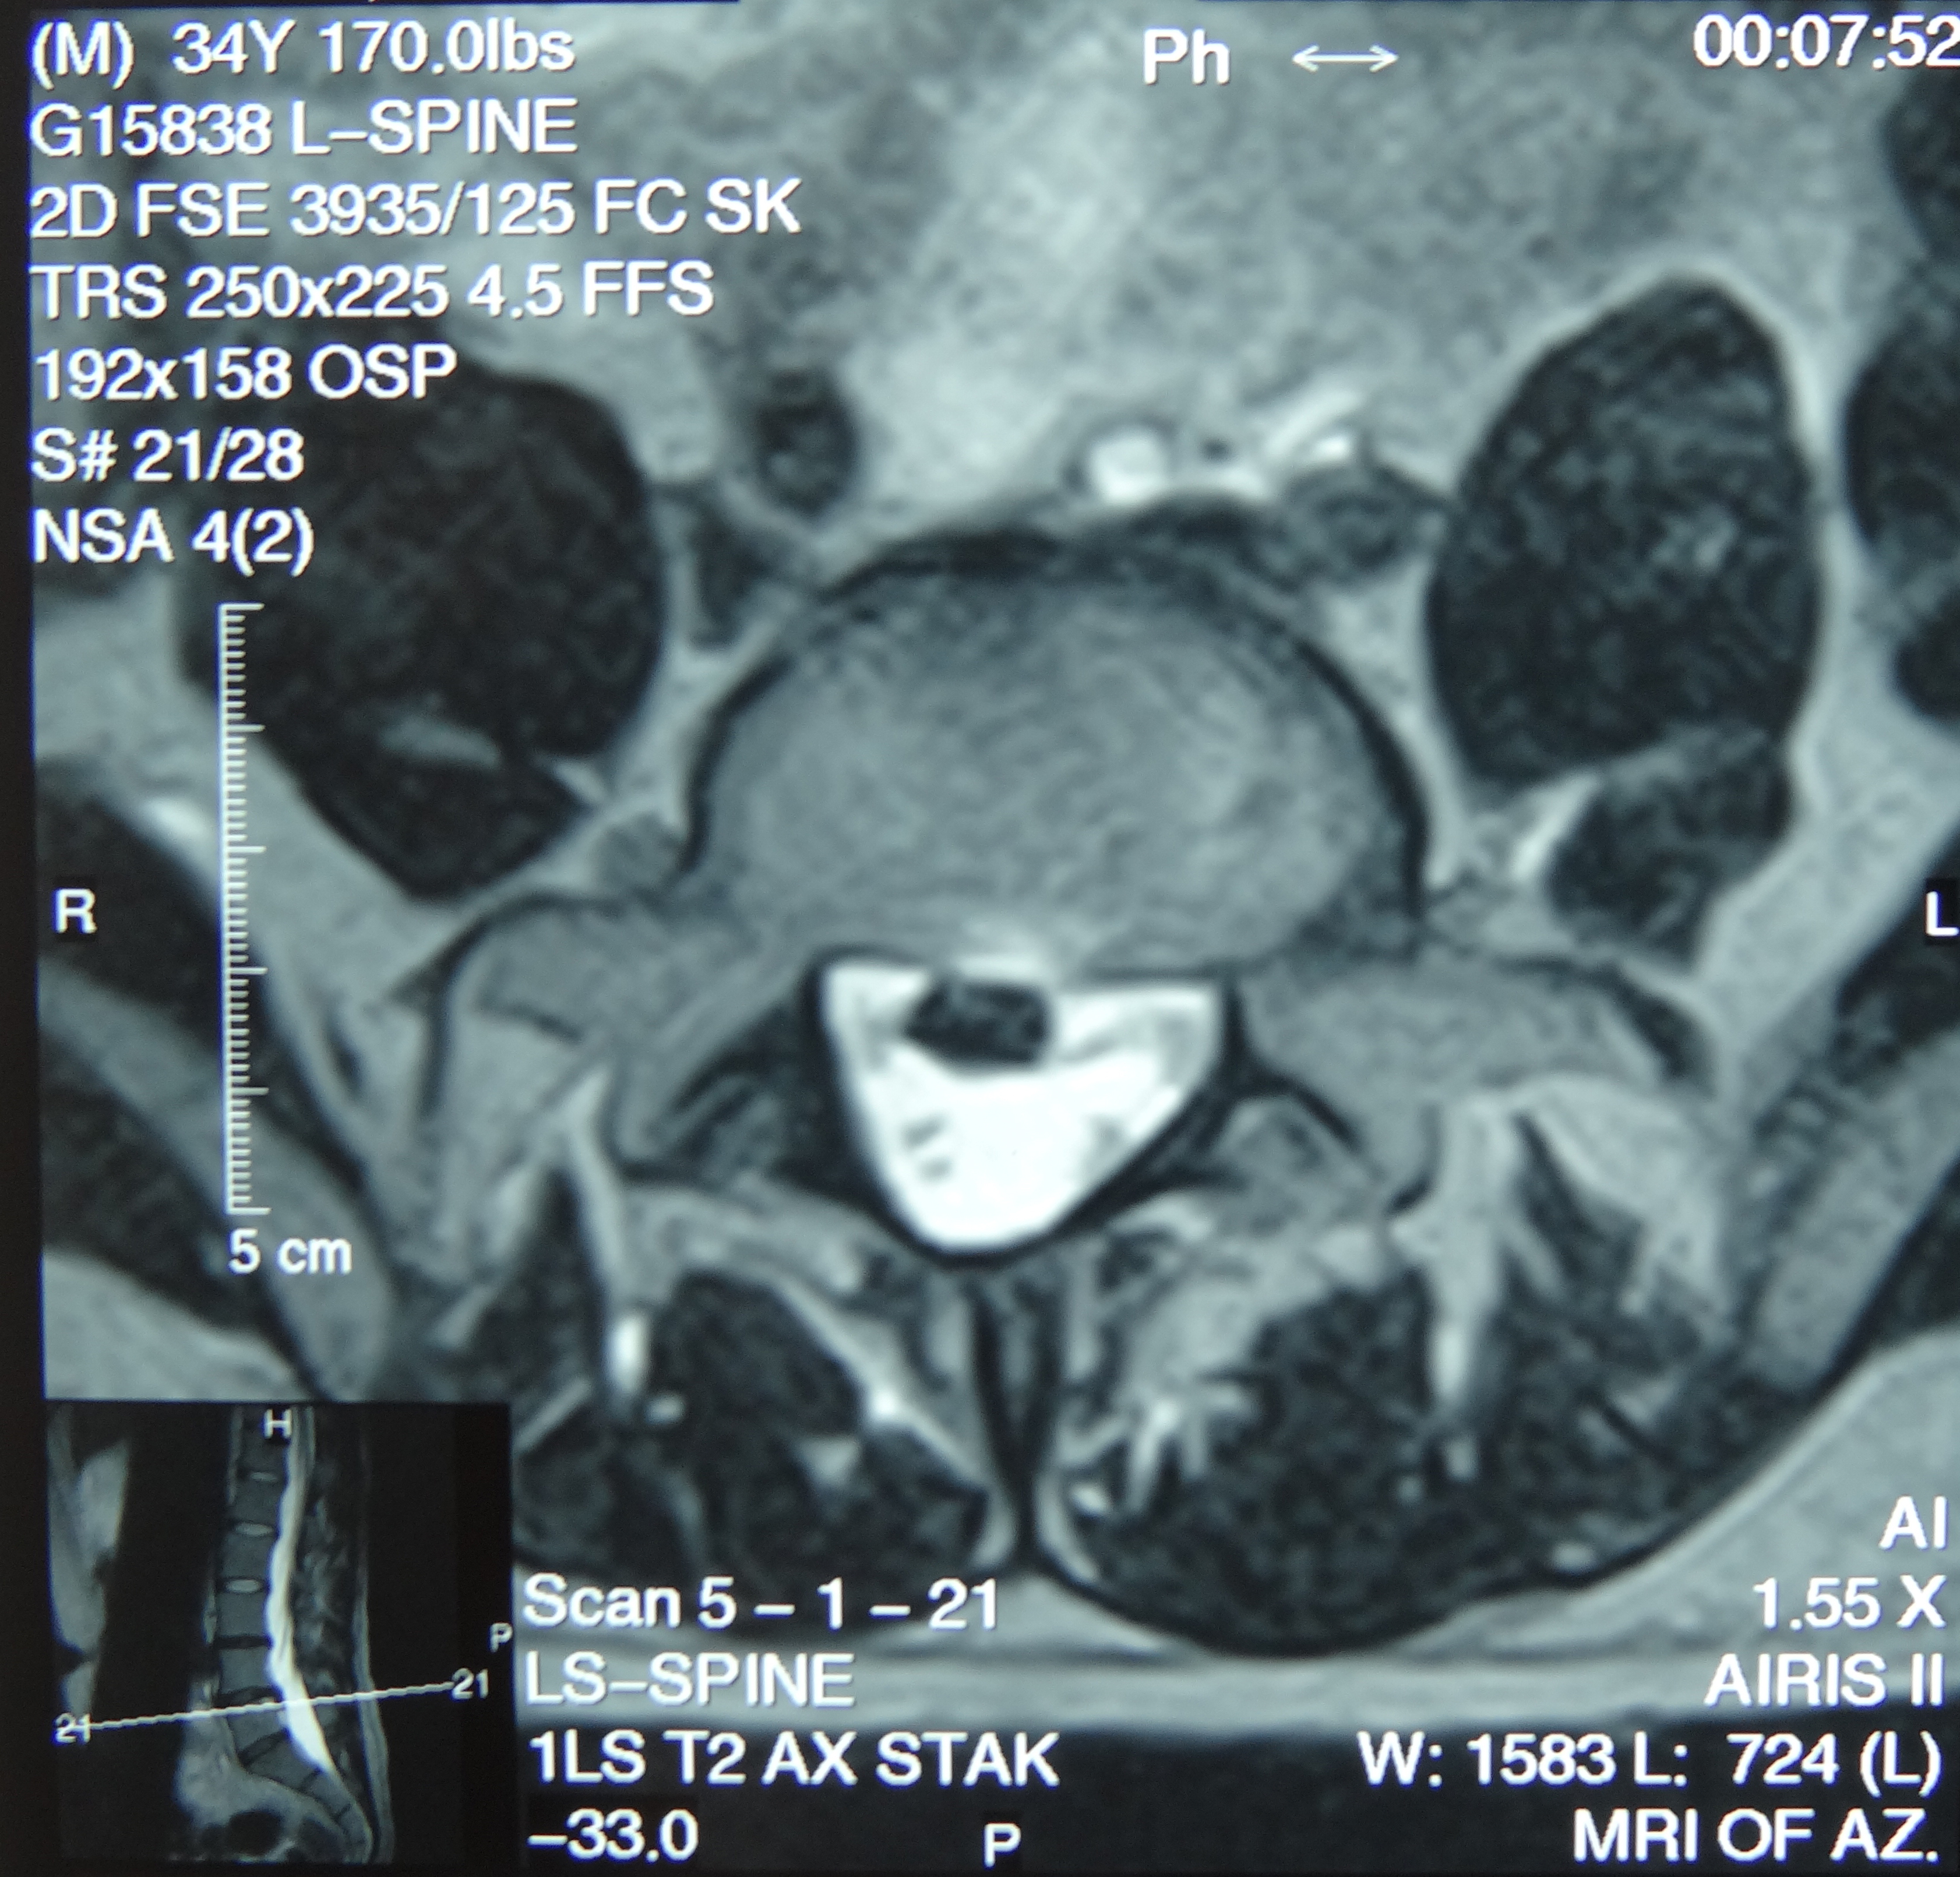

March 2019 MRI

IMPRESSION:

- Complete rupture proximal third anterior cruciate ligament with pivot shift

pattern of bone injuries lateral compartment and contrecoup bone contusion

medial tibial plateau. Joint hemarthrosis. - Complex tear lateral meniscus with inferiorly flipped flap tear extending

into the popliteal hiatus. - Complex tear medial meniscus with outwardly extruded tears of the posterior

horn and body. - Low-grade sprains medial collateral ligament and medial posterior oblique

ligament. - Low-grade sprains fibular collateral ligament and anterolateral ligament.

Intermediate to high-grade sprain popliteofibular ligament and arcuate ligament. - Grade 1 strains vastus lateralis, short head biceps, sartorius, soleus,

popliteus and anterior compartment muscles.